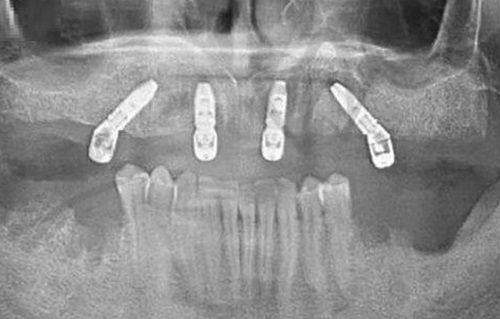

All - on - 4半口种植,9万元起。它采用倾斜植入技术,减少了骨移植需求,还能让患者当天戴牙。这对于半口牙齿缺失的患者来说,既节省了时间,又降低了治疗的复杂性。

相比传统种植,其智能化导板种植是一大亮点。通过CBCT影像 + 3D打印定位模板,能将种植体角度误差控制在±1°内。这就好比我们用高精度的仪器来进行操作,大大提高了种植的正确性,降低了神经损伤风险。就像盖房子一样,基础打得准,房子才能更稳固。